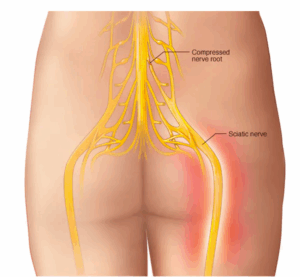

Sciatica

Sciatica refers to pain that travels along the path of the sciatic nerve. The sciatic nerve travels from the buttocks and down each leg.